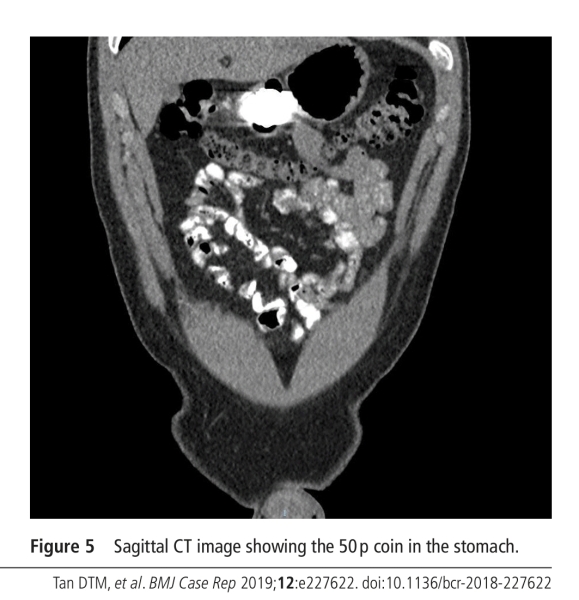

It will not pass his Pylorus, it's too small. Any decent gastroenterologist will clearly tell u anything over 20 mm diameter is not going to pass. The others will tell you it will pass. In 2018 a man swallowed a 50p and a 5p. He passed the 5p the 50p has migrated into the gastric Mucosa. It will errode in gastric fluid, which is hydrochloric acid. Releasing NiCl², this is used in CT and MRI phantoms, it simulates bones etc. it is a fluid solution in this use. It's absorbed in to the tissue at 25-27% during fasting and will making diagnostic imaging difficult as the tissue will become denser that the Copper that's left, it will contain voids filled with hydrogen gas. These cause lucencies in diagnostic imaging. Look at case " Coin migrated into gastric Mucosa" the stomach is after only a few weeks denser than the coin, they only accepted it was the coin as the first image showed the coin. The material that leaches is a group one carcinogen, I have written a paper on this. But as I'm not a Dr I can't get it published, I've just spent the last 44 years conducting experiments in the EMS (electro magnetic spectrum). Of which X-rays are a part of. Coin needs removing via gastric resection. I can link my paper if you want, it contains all the reference data(papers links).

sadly with the Case locally the patient is labelled delusional as it's not visible on imaging. I've included endoscopic image showing it and the professor of gastroenterology states it's food, I've included a 50p I've soaked in HCl and this has developed a patina, it's oxidised and on green. Which is what's happened to the coin in the fundus, that's dismissed as food.

Now I'm going to attach photographs from the original article which highlighted the gentleman had swallowed the coin two and a half weeks before he attended the hospital. One and a half weeks after that he returned again still not having excreted the coin so we are now talking four weeks. And they further 6 weeks after the og the coin still has not been excreted and we are talking 10 weeks. And the coin has not passed through an adult. This is because the adult stomach is too large to push the coin through the Pylorus, because when it shrinks back to its smallist dimensions it is too large to actually apply sufficient pressure to force the coin through the Pylorus.

I have consulted an associate who is a prominent gastroenterologist and he himself has doubts that a two-year-old would pass the coin. This is due to the size and most gastroenterologists are blatantly told that anything over 20 mm is very unlikely to leave the stomach and this would be for the reasons I highlighted previously. Unless you have physically seen the coin with your own eyes in the child's feces. An x-ray will not be conclusive for the reasons I have highlighted, the way you'll be able to check is if your child or the person who has ingested the coin, develops psoriasis, as the released nickel is known to cause this, furthermore they will develop issues with their lymphatic system because the nickel migrates to the lymphatic drainage system where it will cause pastels around the lymph nodes, swelling of the lymph nodes and cutaneous lesions around them. You'll also find green scaly skin probably around the elbows which is a high maintenance area and as a result seems to attract the accumulation of the nickel components, if you apply dermal 500 lotion to this scaly material and scrape it off after a few mins you will end up with a green cream. See attached images, I have actually included an image of regurgitated fluid from the affected individual stomach the clear stuff is gastric fluid and the other staff is blood caused by bleeding and the circle patch is a section of the gastric mucosus which has been cut out by the coin pictures of the coin institute, I have also included the fundus image, showing the coin buried in the gastric mucosa and the little cut out which was circled in one of the attached pictures.